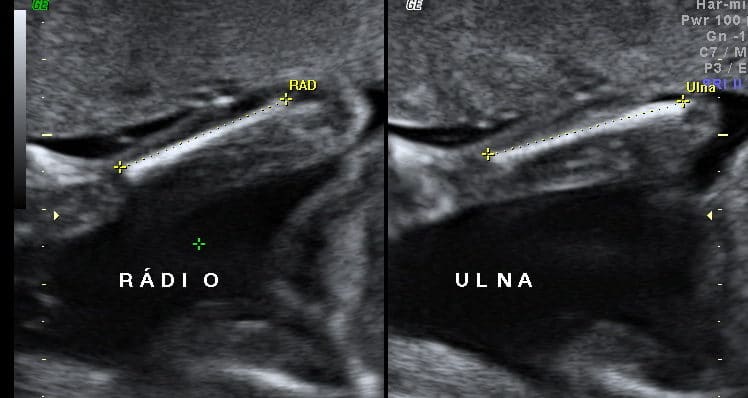

As displasias esqueléticas constituem um grupo heterogêneo de doenças nas quais encontramos alterações da forma, tamanho e constituição dos ossos…